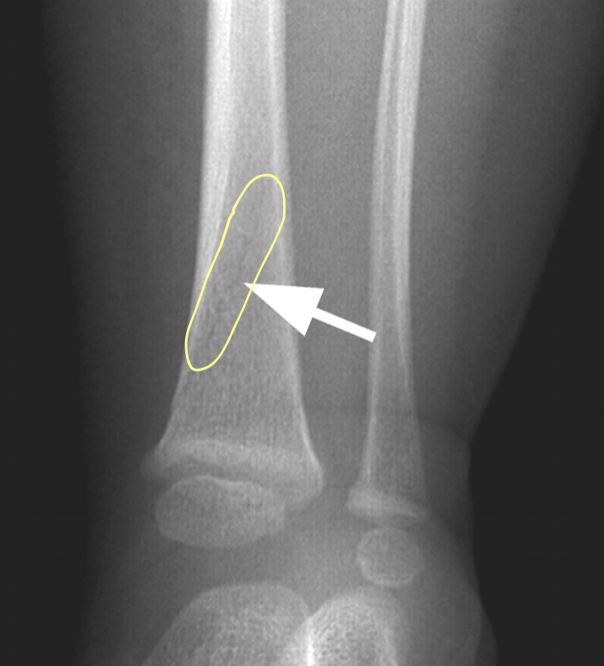

hairline fracture of the tibia

Toddler’s fracture

- in 10-14 days, radiographic evidence of callus formation is present